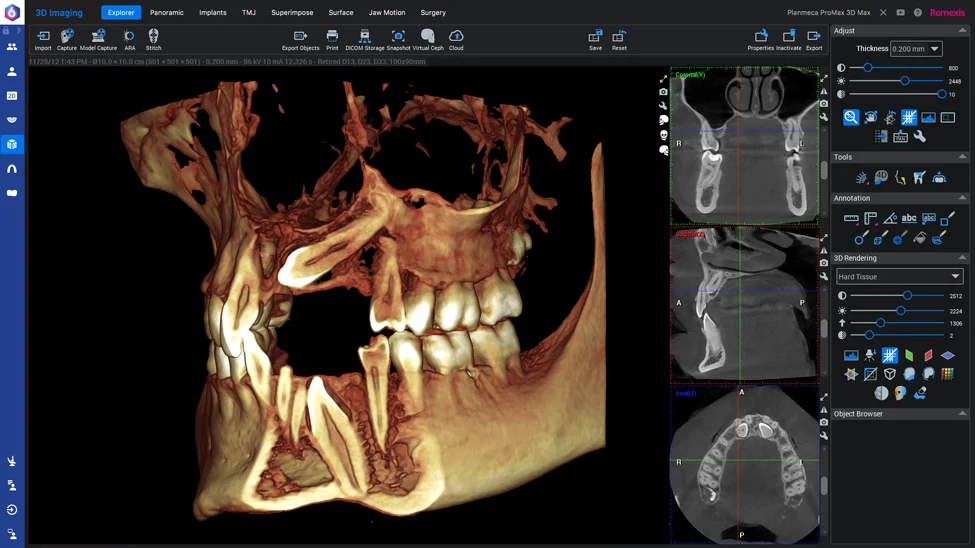

1. Radiografia 3D si consultatia initiala

ETAPA 1: Radiografia 3D si Consultatia Initiala

Cea mai buna varianta pentru fiecare pacient se poate determina doar dupa ce vedem acel computer tomograf 3D, iar atunci putem determina corect numarul de implanturi necesare, tipul implanturilor, cat si necesitatea sau nu a altor proceduri precum aditiile de os sau ridicarea de sinus.